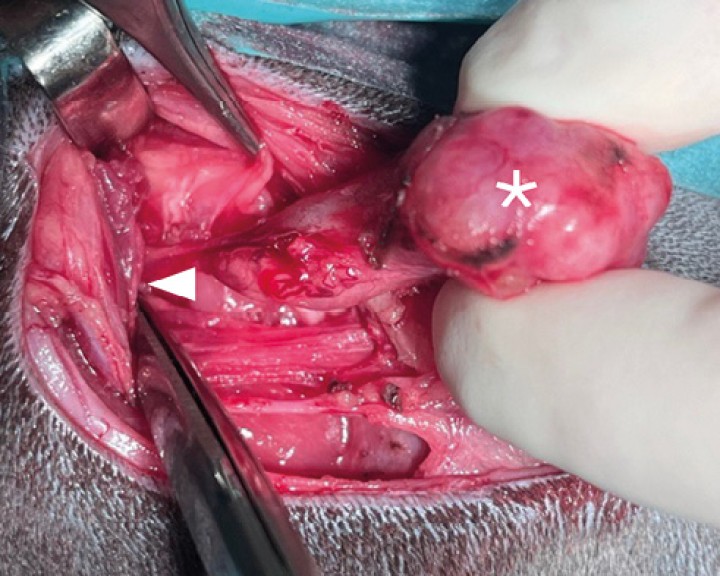

Disección de la glándula mandibular ( * ) junto con la glándula sublingual del resto de tejidos. Durante la disección es necesario realizar hemostasia mediante ligadura o diatermia de la vascularización que irriga a dicho complejo salivar. La disección del complejo debe realizarse paralela y rostralmente exponiendo los pequeños grupos de tejido salivar de la glándula sublingual hasta su aspecto más rostral. Los conductos salivales deben ser diseccionados hasta la rama lingual ( < ) del nervio trigémino. Llegados a esta localización se realiza la ligadura distal del conducto mientras se tracciona ligeramente del complejo salivar con el fin de facilitar su exposición.